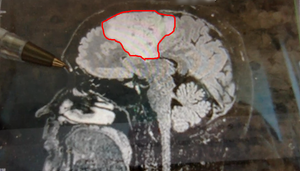

Meet my tumor

Time to cut to the chase. This is my brain tumor. There are many like it, but this one is mine. I've nicknamed him Gary Glia. Gary because it is a seemingly unpopular name nowadays in the UK (can't imagine why...), so it seemed quite appropriate. And Glia because it is the type of cell in my brain that has gone tumorous.

Gary is an unpaying tenant that has taken up residence in my head. What a prick!

A few days later I had a meeting with the neurosurgeon where I was shown the above images. Now full respect to the neurosurgeon I spoke too, I like him. He was straight down the line and straight to the point. No sugar coating, no forewarning about the size of the tumor. After 30 minutes of chatting about all of the above, he simply pulled his phone out and showed me image number 1 you see above. You could say I wasn't exactly prepared for the image, a understatement if ever there was one. But in all honesty I don't think I ever would be. So it was a good tactic. Make it quick and painless, just like ripping off a band-aid!

So, what do we know about Gary?

- He's big... look at the size of this unit. I'm amazed I can even function at all to be honest!

- He's of the type called oligodendroglioma and currently believed to be a Grade 2 (slow growing) tumor. Wondering how you pronounce that? Isn't YouTube great!

- He's very rare, with only 1,217 people diagnosed with this type in the US every year out of a population of 328 million!

- He's a number of years old. The neurosurgeon said a couple of years, but I personally suspect he could be 7 or 8 years old due to other symptoms in my past I now think could be related.

- He's a prick.